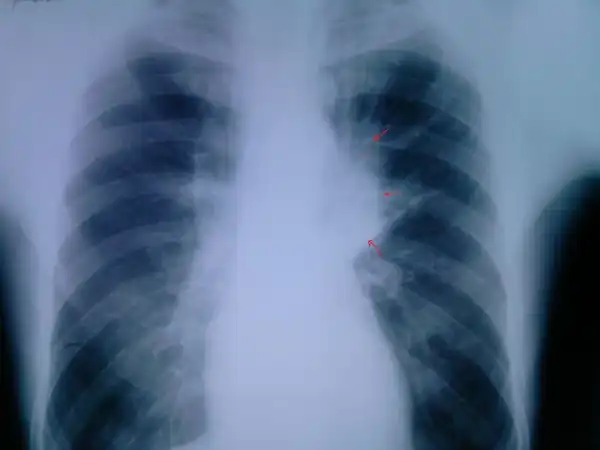

НОРМА: